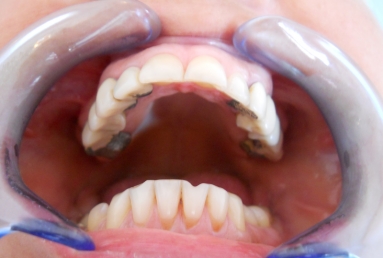

Before treatment: old fractured prosthetic restorations in the lateral maxillary areas made out of metal and composite material, deep bite, frontal maxillary teeth severely inclined.